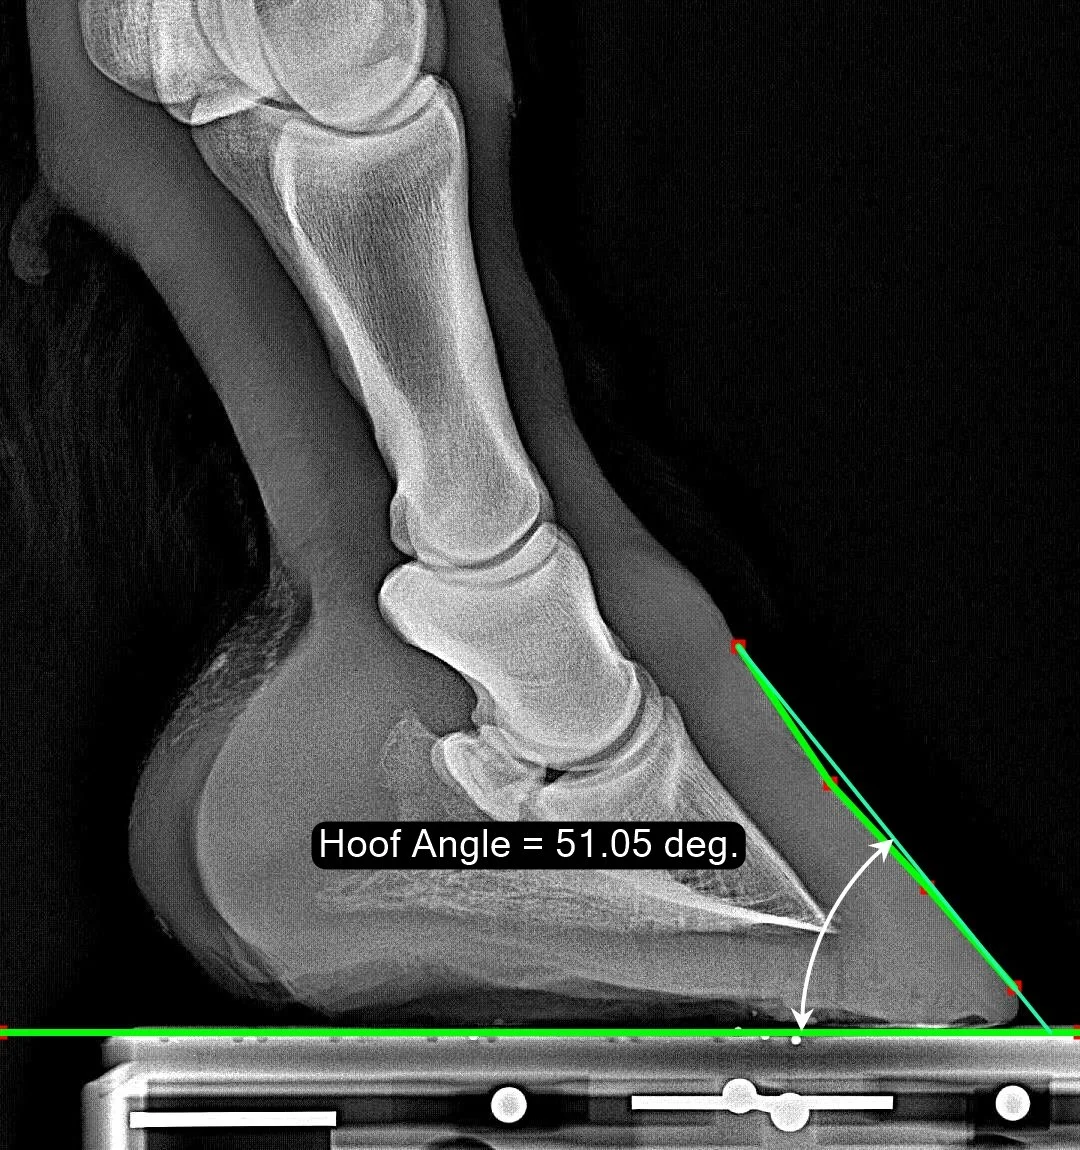

Hoof Angle

The Hoof Angle measurement is measured as if a physical gauge was laid across the dorsal wall of the hoof starting at the coronary band. This means that a “dish” if the hoof is spanned (as you see in this sample image). On a bull-nosed hoof, this scheme may underestimate the Hoof Angle. The Hoof Angle is only perfectly defined when the dorsal hoof wall is straight.

Normal Range

The ‘normal range’ observed in the population ranges from 45 degrees to 53 degrees, with a median of 49.2 degrees.